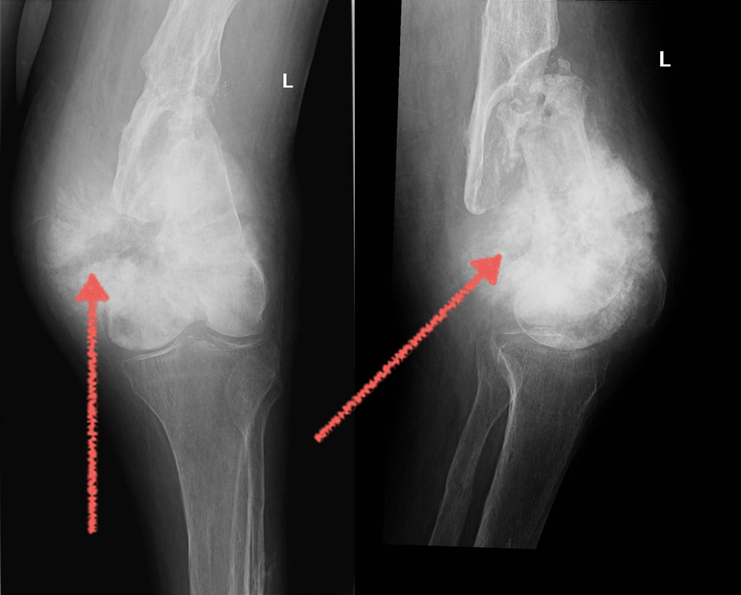

Рентгенологическая картина остеогенной саркомы кости - 98 фото